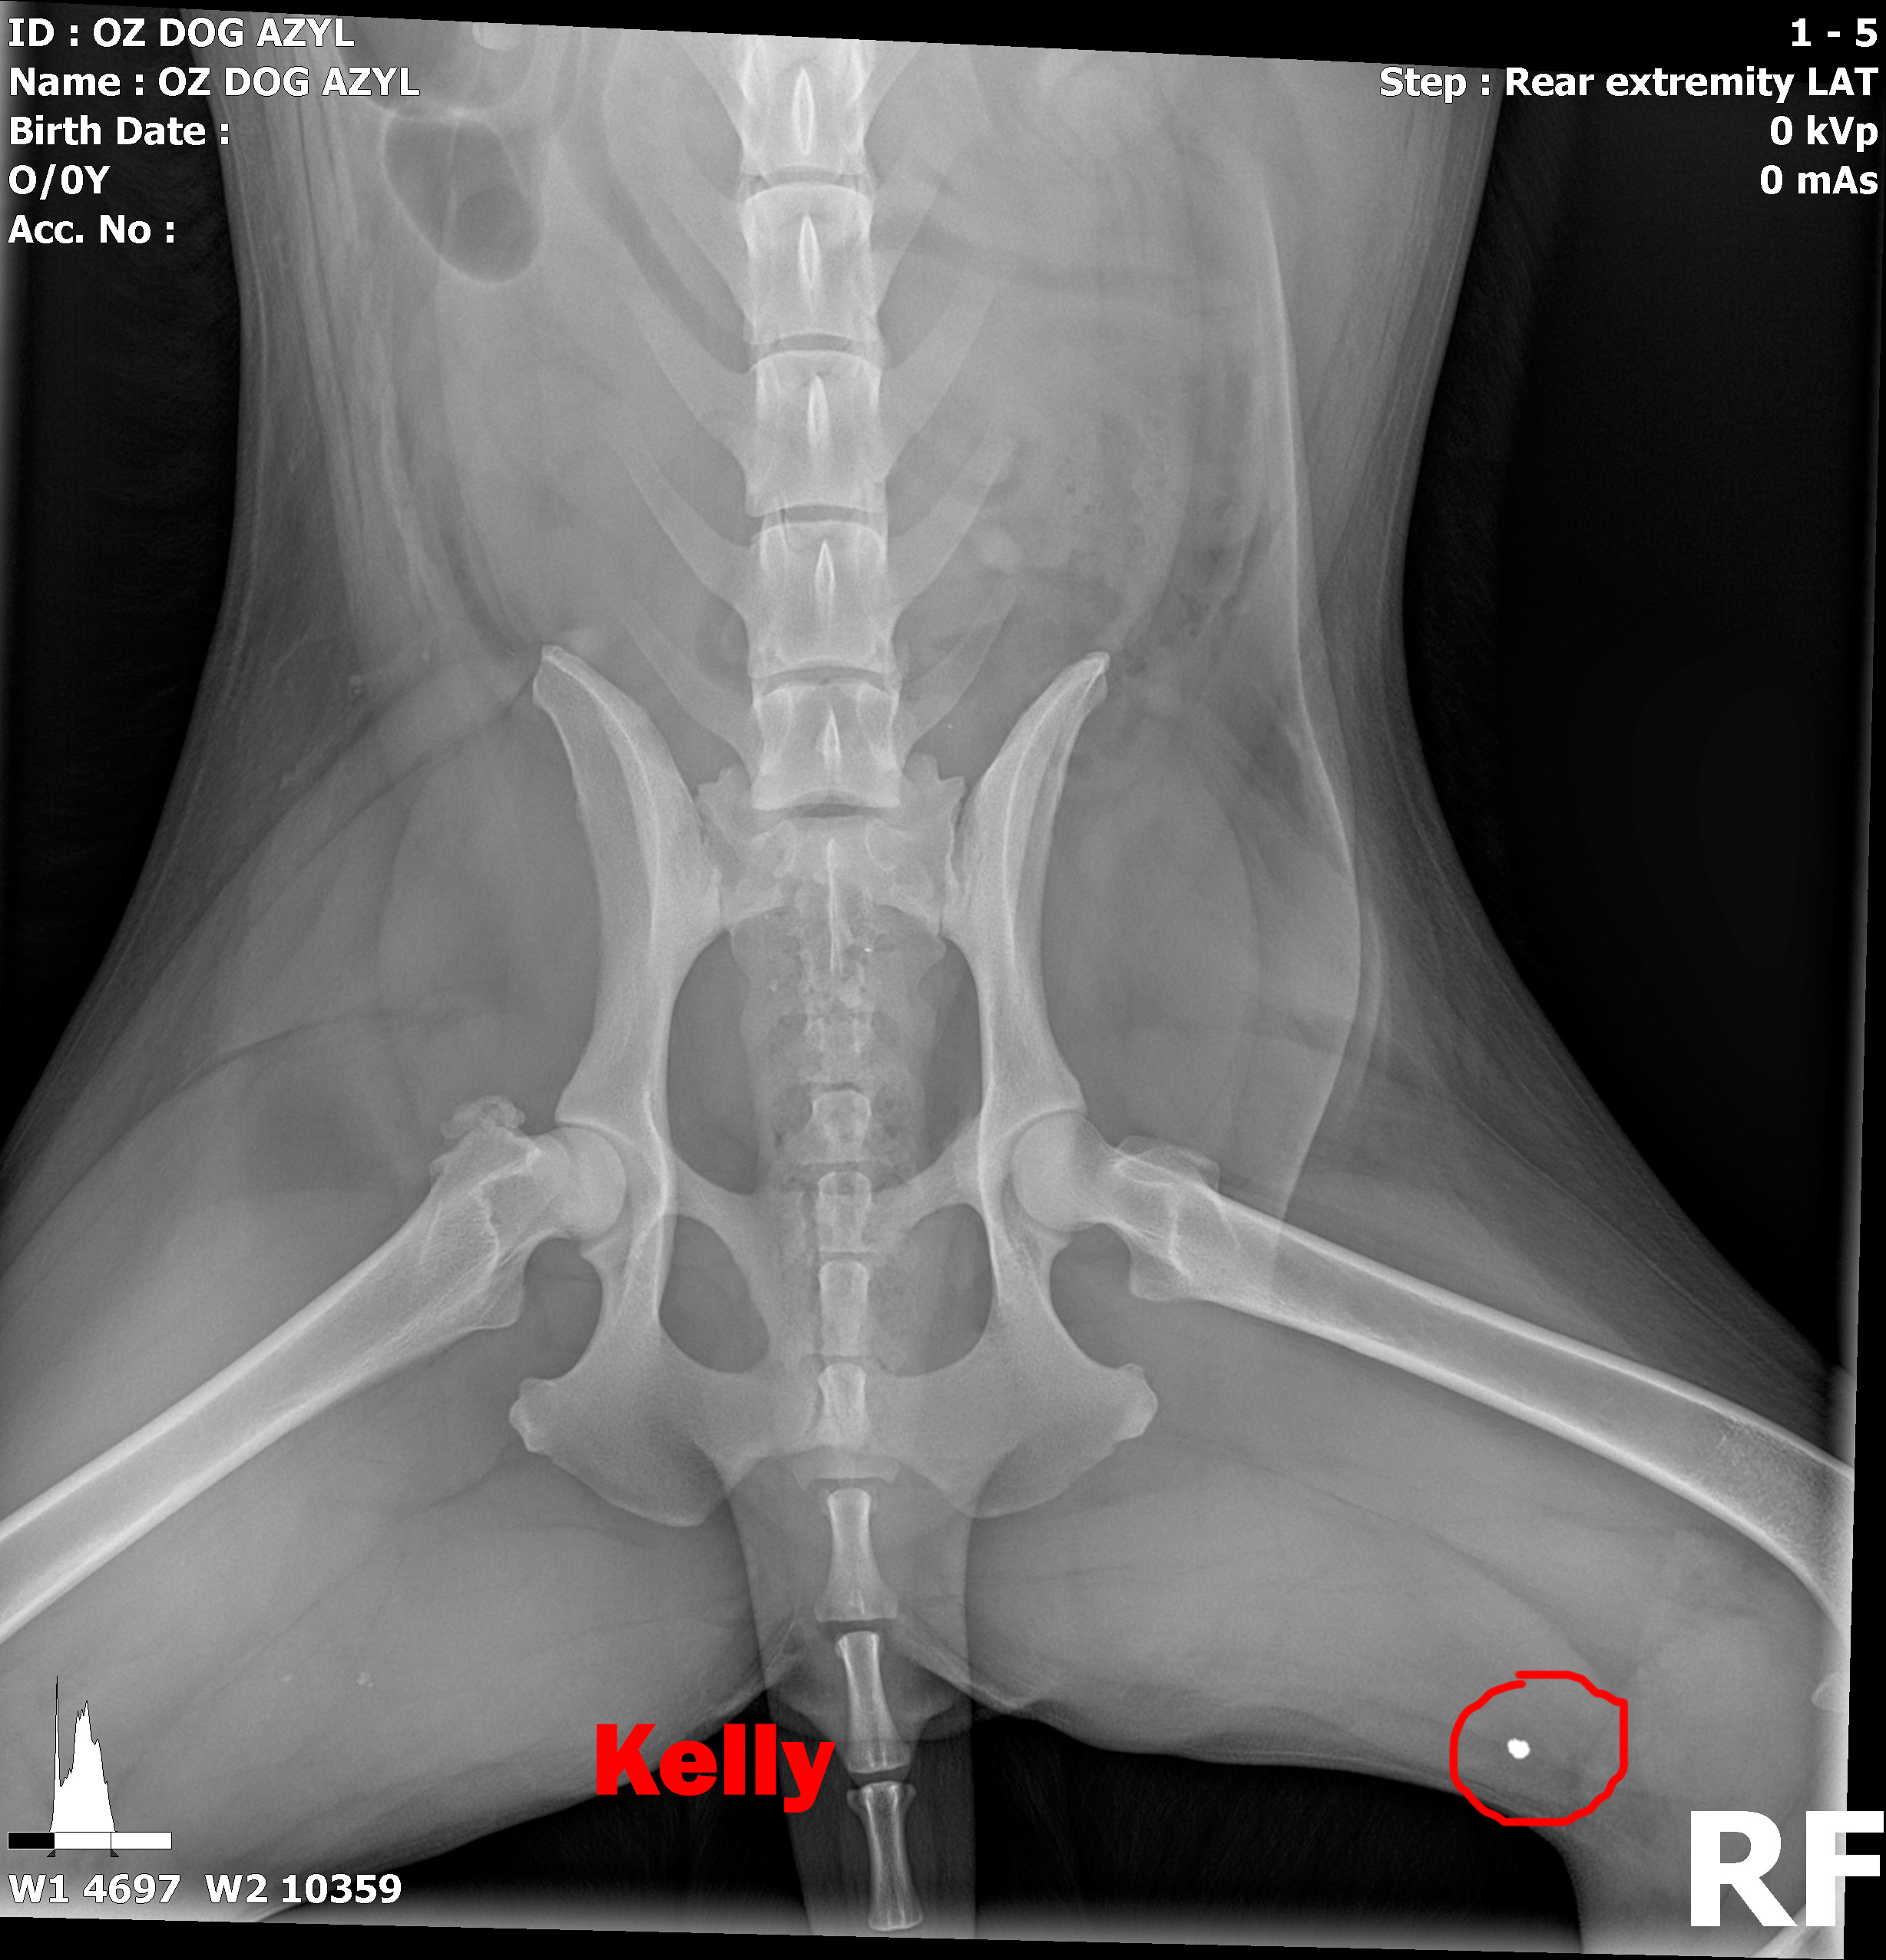

KELLY - Vzali sme ju z ranča, kde boli zvieratá v hororových podmienkach. Neudrží sa na zadných nohách. Môže to spôsobovať hneď niekoľko faktov.

Image removed.KELLY - Vzali sme ju v rámci záchrannej akcie ČSKP z ranča, kde boli zvieratá v hororových podmienkach. Jedli, čo si našli, nekontrolovane sa medzi sebou množili a vôbec nie je vylúčené, že aj na ostatných si nejaký zlomyslený človek skúšal streľbu do diaľky. Kelly je úžasná, pokorná, mierumilovná, oddaná fenka, ktorá sa tak strašne zmierila s utrpením a svojim životom, že celé dni len tíško preleží v peliešku a občas si poplačká. Užíva si každé pohladenie, ale nechce byť nenásytná lebo nevie, či sa jej aj zajtra ujde. Ťažko je ju pohladiť bez toho aby Vám pri nej slza nevytiekla. Nevieme a nechceme si ani len predstaviť akým peklom si musela už prejsť. Kelly má diagnóz hneď niekoľko. Jej primárnym problémom je hrozné krívanie, doslova hopká ako zajko. Neudrží sa na zadných nohách. Môže to spôsobovať hneď niekoľko faktov.

V ľavej packe, medzi druhým a tretím prstom mala brok (treba si to predstaviť, ako keď máte kamienok v topánke a nech stúpate akokoľvek, vždy Vás tlačí. Lenže to je len kamienok a nie cudzí predmet v živom tkanive. Tú bolesť si radšej ani nepredstavujte.) V tej istej nožičke, v oblasti zadnej strany kolena bol ďalší brok, ktorý jej tiež prekážal pri narovnaní nohy. Prvým krokom bolo odstránenie týchto dvoch brokov, ktoré pravdepodobne spôsobovali najväčšie ťažkosti. Operácia sa konala 10.5.2020, dopadla výborne, Kelly sa zotavuje.

Píšeme ale "pravdepodobne" preto, lebo Kelly má tiež problém s krížovým väzom v kolene, ktorý má známky deformácie a má tiež hypointenzitu disku (to znamená, že má na platničke medzi stavcami pruh, ktorý vyčnieva a tlačí na miechu). Veríme, že vsetci strážni anjeli pri nej budú stáť a zvládne sa zotaviť, aby si mohla užívať taký život, aký mala žiť od narodenia. My sme pri nej, zabezpečíme jej všetko potrebné! Za diagnostiku, MRI a chirurgiu máme dve faktúrky, v celkovej výške 762,05€.